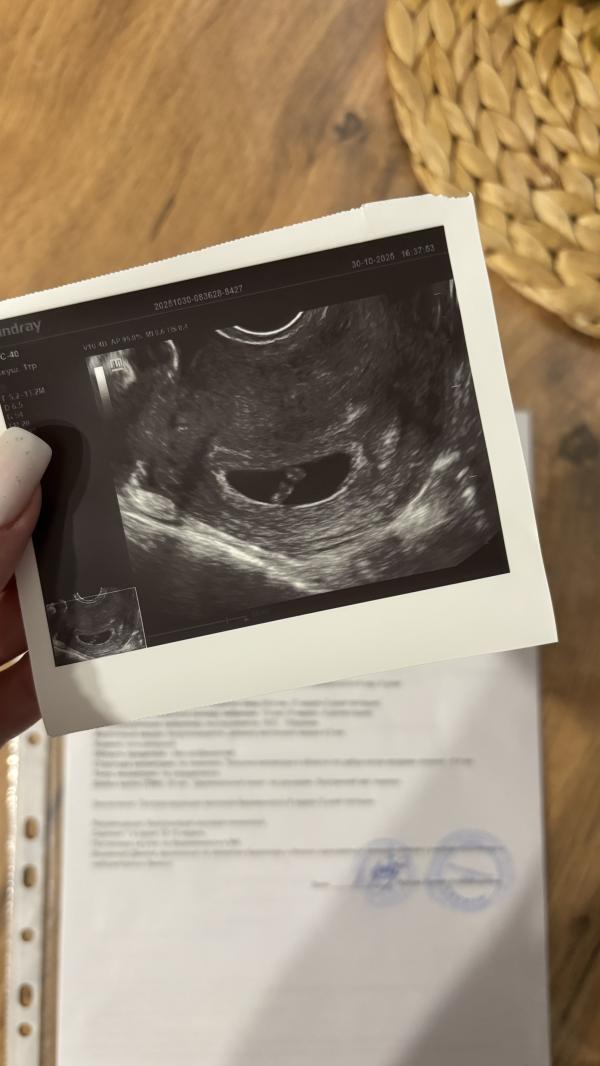

Вчера была на узи. Чтоб узнать бьется ли сердечко. Все хорошо, малыш подрос, сердечко стучит.